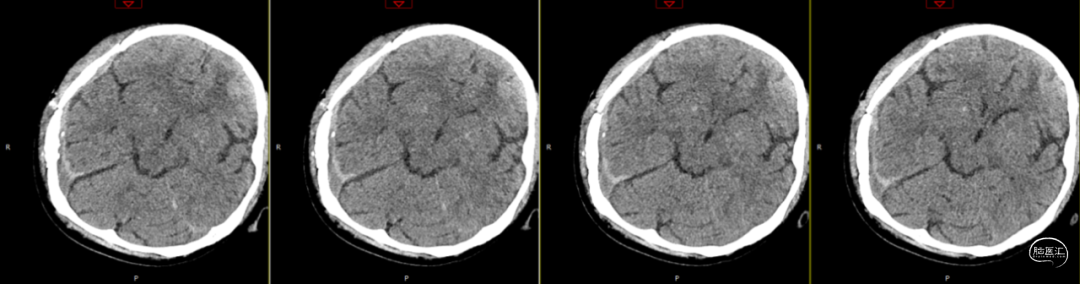

2024-07-21 08:58:55术后58天复查(如上图)。

术后58天颅脑磁共振平扫(如上图):右侧额顶颞部见斑片状异常信号,呈片状T1WI低、T2WI稍高信号影,T2FLAIR呈稍高信号,边界清,右侧额顶颞叶脑组织受压,DWI(b=1000)呈混杂高信号,相应ADC呈混杂高信号影。